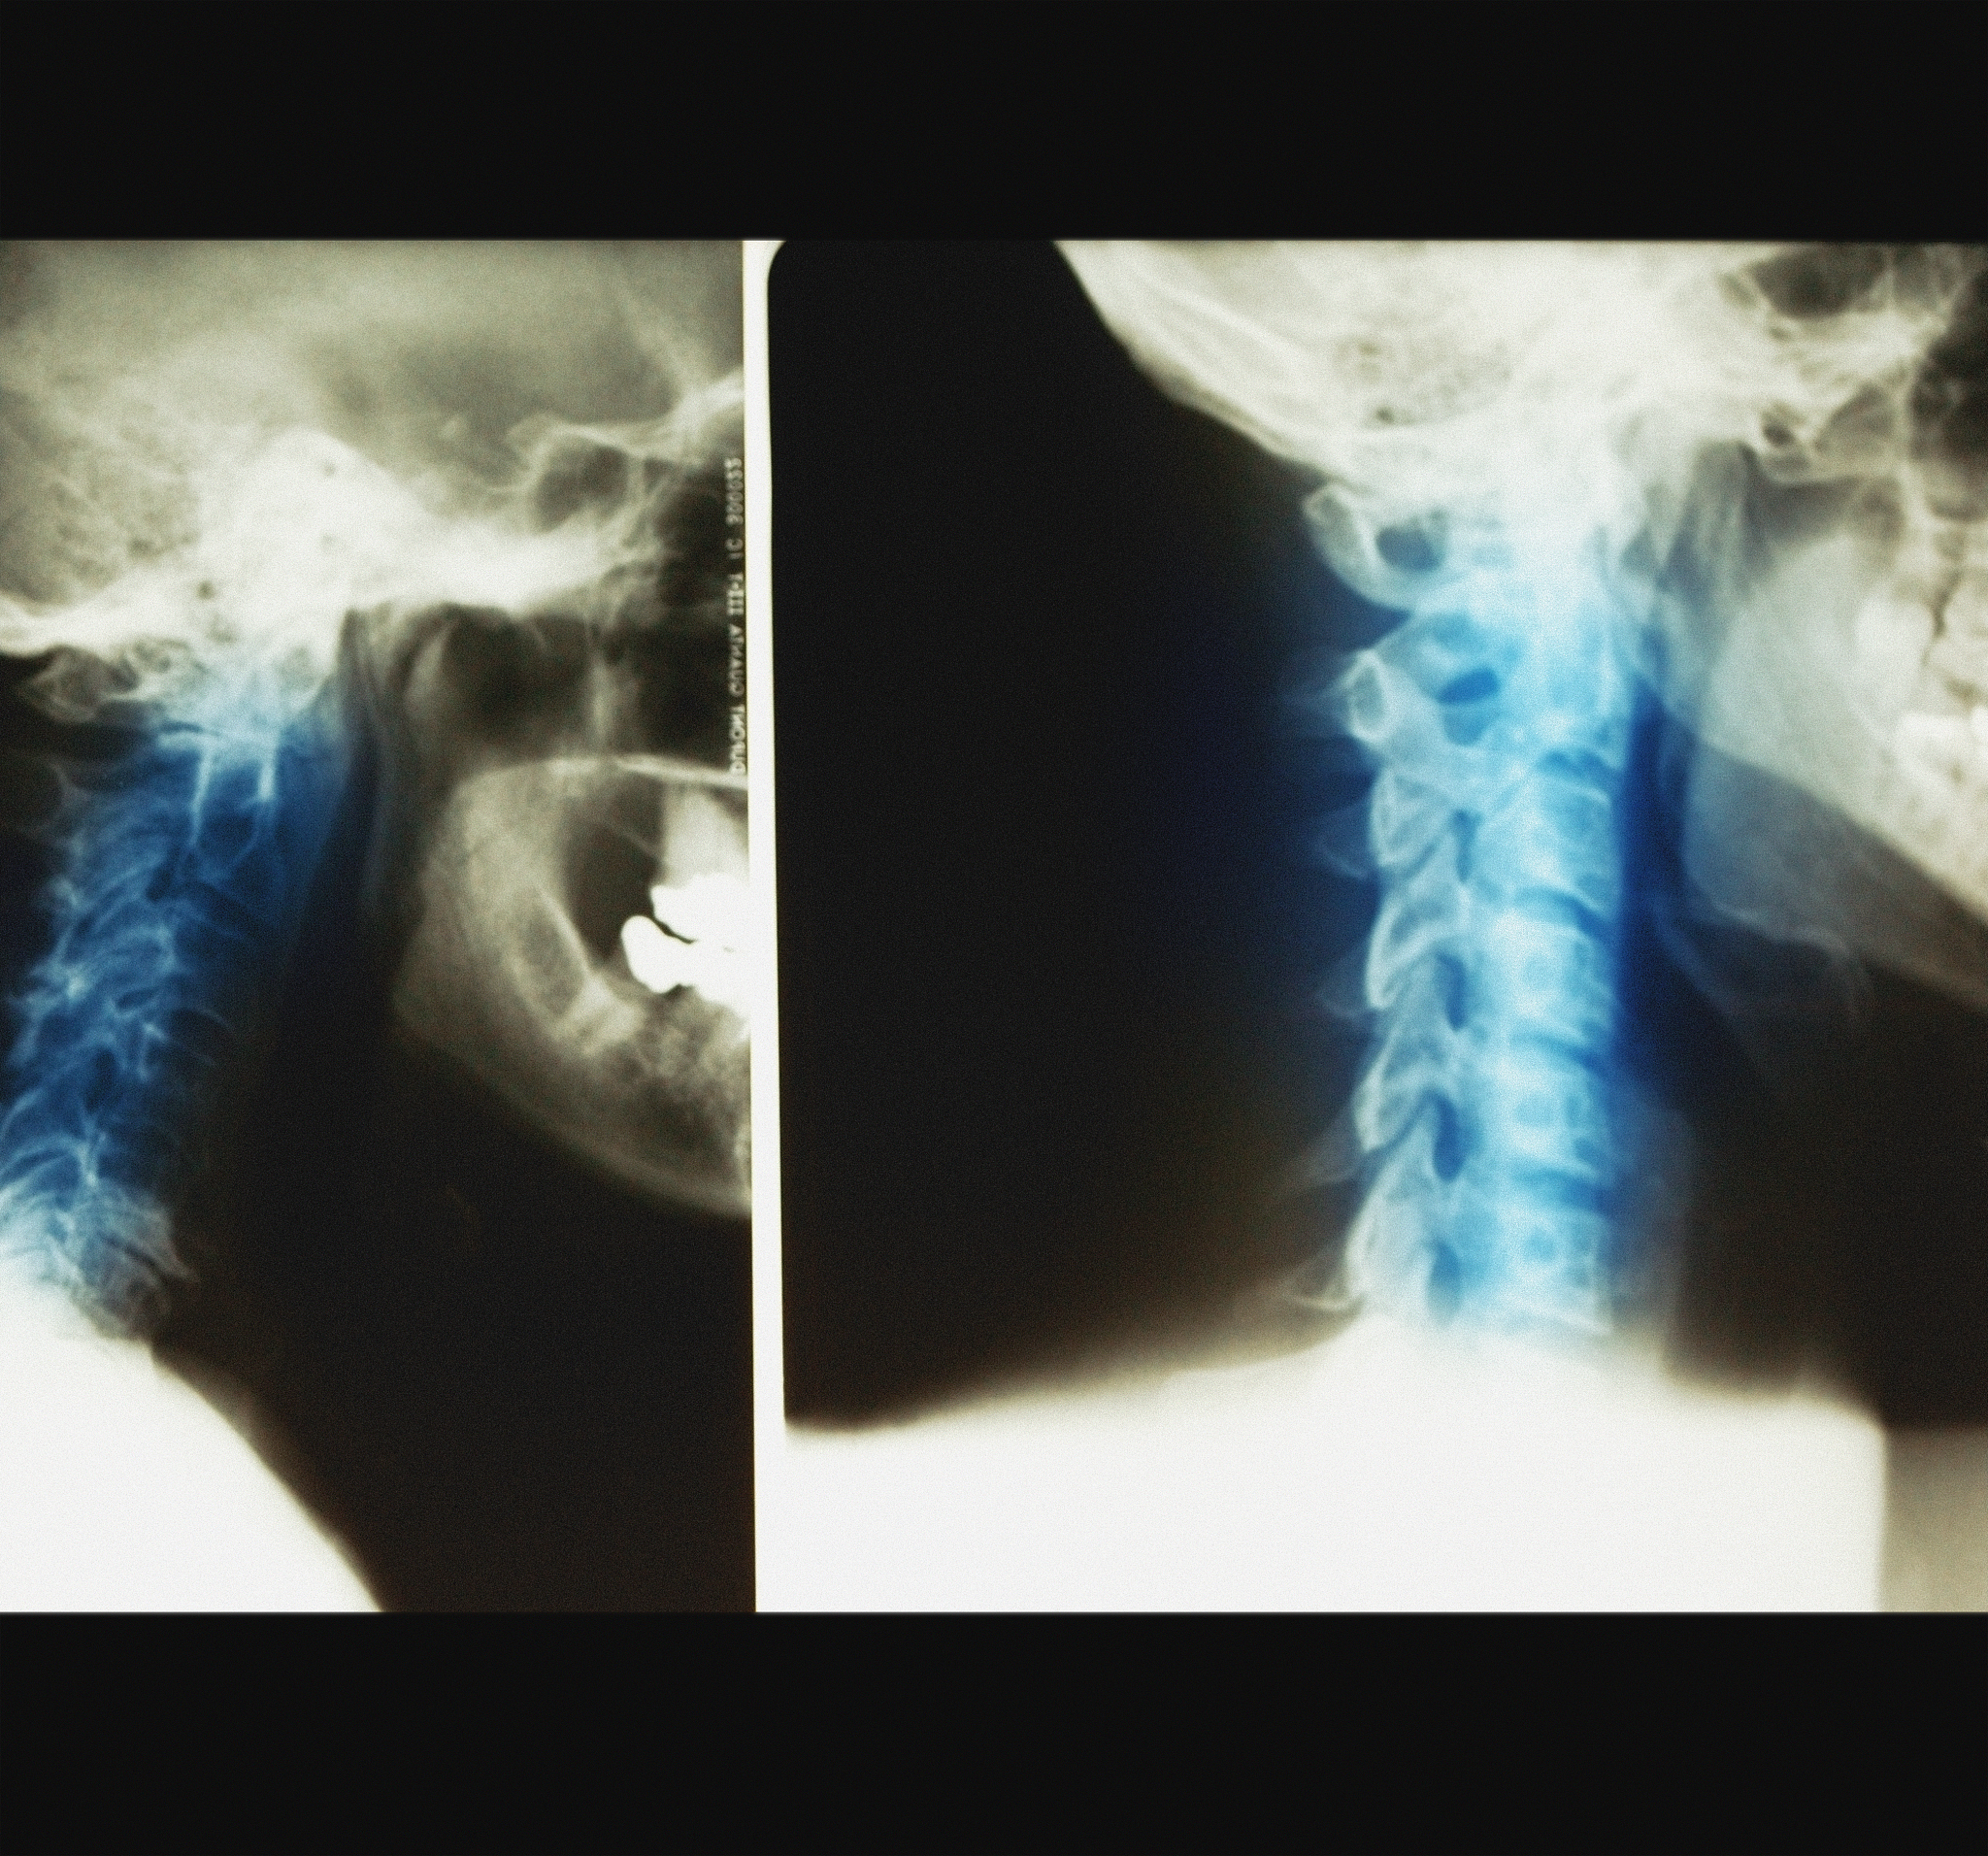

2. 颈椎扭伤:过山车的剧烈晃动和颠簸可能会导致颈椎扭伤,引起脖子酸痛和不适。

3. 颈椎关节紊乱:过山车的震动和颠簸可能会导致颈椎关节紊乱,引起脖子酸痛。